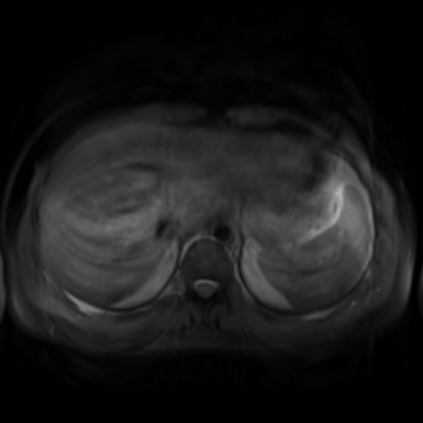

Motion artifacts are a primary source of magnetic resonance (MR) image quality deterioration with strong repercussions on diagnostic performance. Currently, MR motion correction is carried out either prospectively, with the help of motion tracking systems, or retrospectively by mainly utilizing computationally expensive iterative algorithms. In this paper, we utilize a novel adversarial framework, titled MedGAN, for the joint retrospective correction of rigid and non-rigid motion artifacts in different body regions and without the need for a reference image. MedGAN utilizes a unique combination of non-adversarial losses and a novel generator architecture to capture the textures and fine-detailed structures of the desired artifacts-free MR images. Quantitative and qualitative comparisons with other adversarial techniques have illustrated the proposed model's superior performance.

翻译:移动文物是磁共振(MR)图像质量恶化的一个主要来源,对诊断性能产生强烈影响。目前,MR运动的校正要么是预期性的,借助运动跟踪系统,要么是追溯性的,主要是利用成本昂贵的计算迭代算法。在本文中,我们使用名为MedGAN的新颖的对抗性框架,联合追溯性地校正不同身体区域的硬性和非硬性运动文物,而不需要参考图像。 MedGAN利用非对抗性损失和新型生成器结构的独特组合来捕捉无MR图象的纹理和精细详细结构。 与其他对抗性技术的定量和定性比较展示了拟议模型的优异性表现。